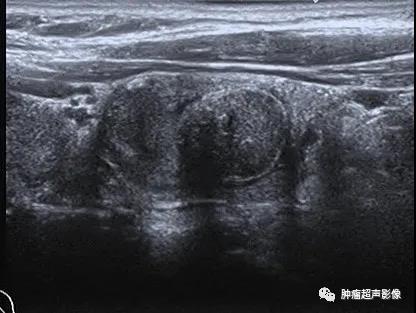

甲状腺下极结节,病史不明,呈低回声,边缘尚光整,内见点状强回声及彗星样强回声,内部无血流,超声造影显示无增强,从而增加诊断皱缩结节的信心,避免穿刺及手术。

“蛋壳样钙化”,无血流,超声造影光滑的无增强,考虑皱缩结节。